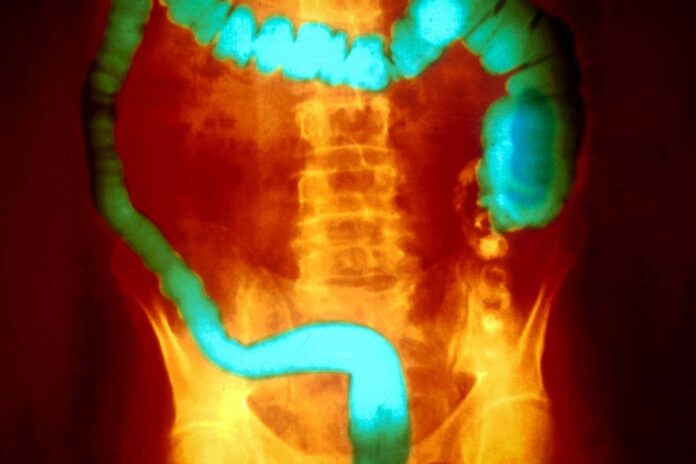

Язвенный колит характеризуется хроническим воспалением толстой и прямой кишки, часто чередующимся между периодами без симптомов и тяжелыми обострениями. Точные причины заболевания оставались загадкой, хотя частично связаны с аутоиммунными реакциями, генетикой и экологическими факторами. Исследователи теперь считают, что макрофаги — иммунные клетки, ответственные за очистку от мусора и регулирование воспаления, — являются ключом к пониманию прогрессирования заболевания.

Макрофаги действуют как привратники, поднимая тревогу, когда необходимо воспаление, но также сигнализируя о возврате к спокойствию. Исследования показывают, что у пациентов с язвенным колитом значительно меньше макрофагов в ткани толстой кишки. Эксперименты на мышах подтвердили, что устранение этих клеток сделало их более восприимчивыми к развитию колита, что позволяет предположить, что истощение макрофагов напрямую способствует воспалению кишечника.